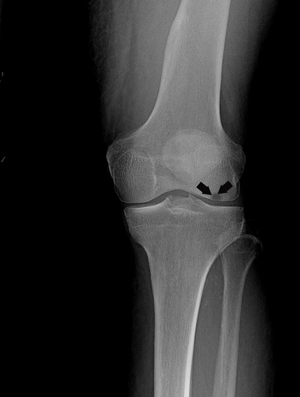

Osteonecrosis of the knee is most commonly seen in the medial femoral condyle, a projection of the lower end of the femur (thigh bone) present towards the inner side of the knee. The condition can also occur on the outside of the knee (the lateral femoral condyle) or on top of the shinbone (the tibial joint surface), known as the tibial plateau.

There are four stages of development, which can be distinguished by symptoms and X-ray results.

- Stage III: At this stage, the condition becomes clearly visible on X-rays and no other diagnostic tests are required. At this point, the bone itself begins to decay and cartilage covering the bones loosens from other segments of the leg. Surgical treatments are considered at this stage.

- Stage IV: In this stage, the articular cartilage is destroyed, joint space narrows, bone collapses, and bone spurs form. The only treatment at this point is joint replacement surgery.